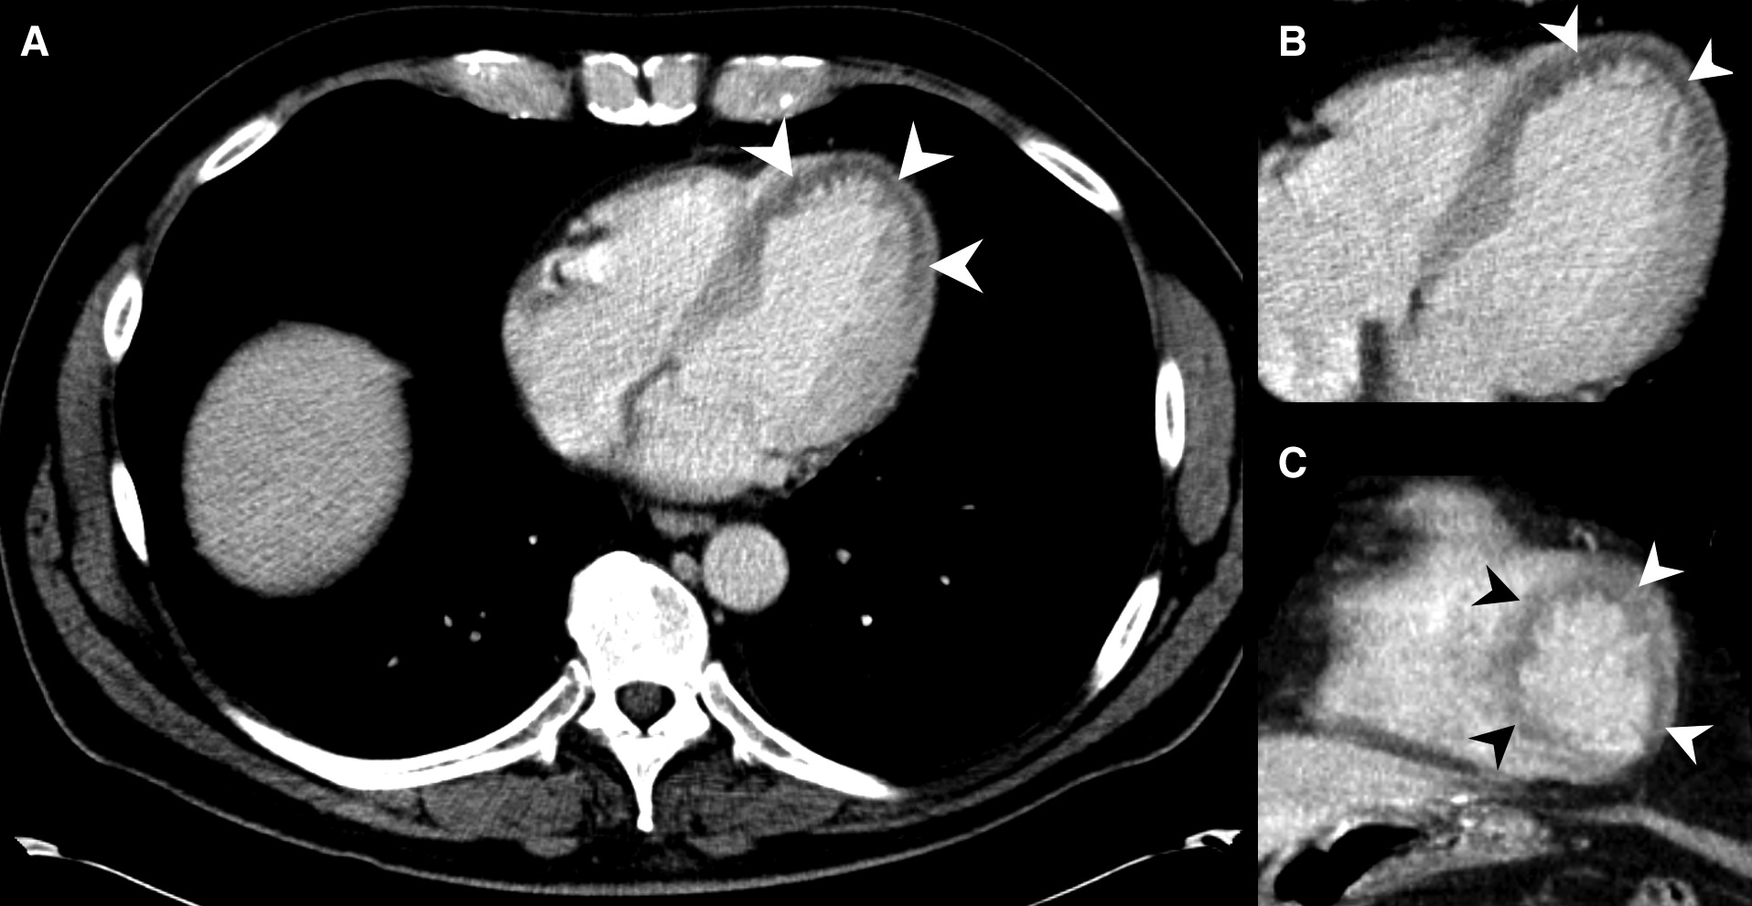

Figure 3

MDCT of a 53-year-old male presenting pain in the chest and upper abdominal area. MH is noted at the left ventricle at the heart apex on axial slices (A,B) and on coronal reformations (C) (arrowheads), but was not described in the radiological report. Emergency doctors clinically suspected MI about one hour after the MDCT, and the patient was transferred to PTCA shortly after. The patient could be discharged from hospital after a few more days.